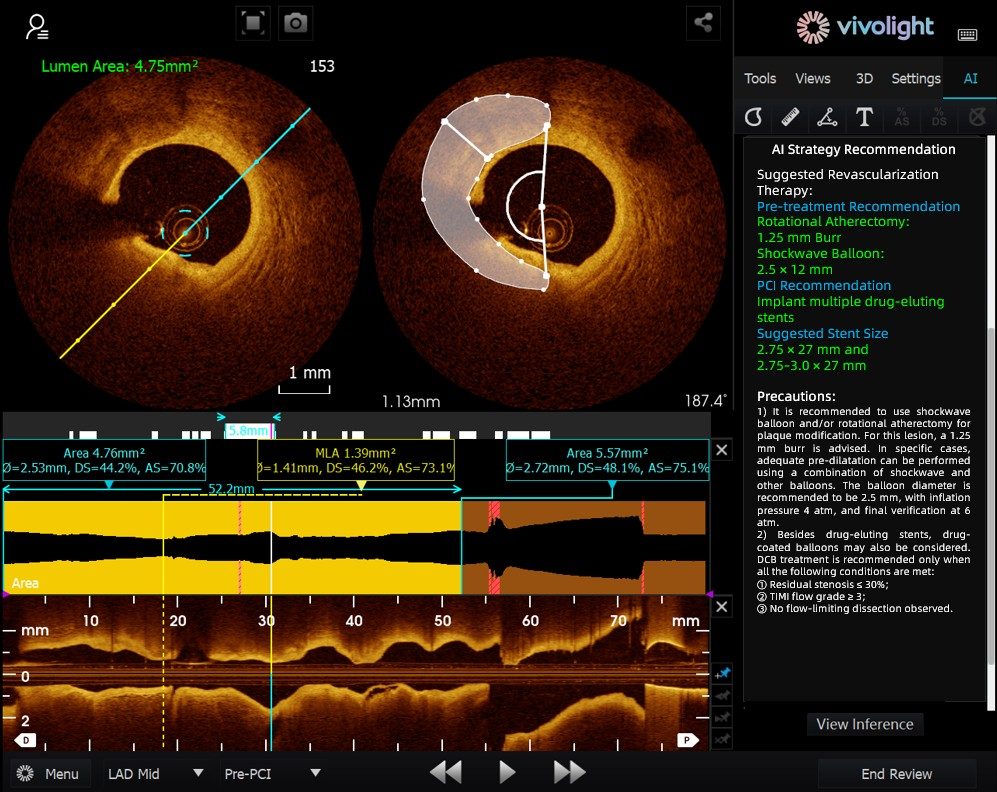

Développé à partir du système OCT de Vivolight Medical, l'AI-OCT est un système d'aide à la décision intelligent de nouvelle génération pour l'imagerie intravasculaire. Il intègre des données diagnostiques d'imagerie intravasculaire dispersées — notamment le diamètre de la lumière, les lésions responsables, l'OCT-FFR et la nature des plaques — afin d'élaborer des stratégies de traitement complètes et des recommandations concrètes. Logiciel de recherche indépendant intégré à la plateforme OCT, il est co-développé avec différents hôpitaux pour créer des versions personnalisées adaptées à des besoins cliniques spécifiques.

Lors de ce forum de pointe, les experts ont souligné que le système AI-OCT représente une transformation majeure, passant de la simple « visualisation d'images » à l'« élaboration de plans de traitement ». Il permet de relever les défis posés par la surcharge d'informations et la complexité des décisions à prendre lors des interventions cardiaques, qui reposent traditionnellement sur l'expérience du médecin. Les principaux avantages de ce système sont les suivants :

●Guidage peropératoire en temps réel : Il organise dynamiquement les informations diagnostiques pendant l'intervention chirurgicale, en fournissant des indicateurs clés et des recommandations cliniques.

●Prise de décision fondée sur des preuves : Toutes les suggestions sont conformes au consensus des experts et aux recommandations cliniques, ce qui garantit rigueur et fiabilité.

Le système AI-OCT adopte une architecture « petit modèle + données massives + grand modèle » : les petits modèles permettent une interprétation précise des images, tandis que les grands modèles sous-tendent un raisonnement clinique complet. S’appuyant sur des bases de données cardiovasculaires de haute qualité et la technologie RAG (Retrieval-Augmented Generation), il offre une prise en charge globale, de l’évaluation des lésions à l’élaboration de la stratégie de traitement.